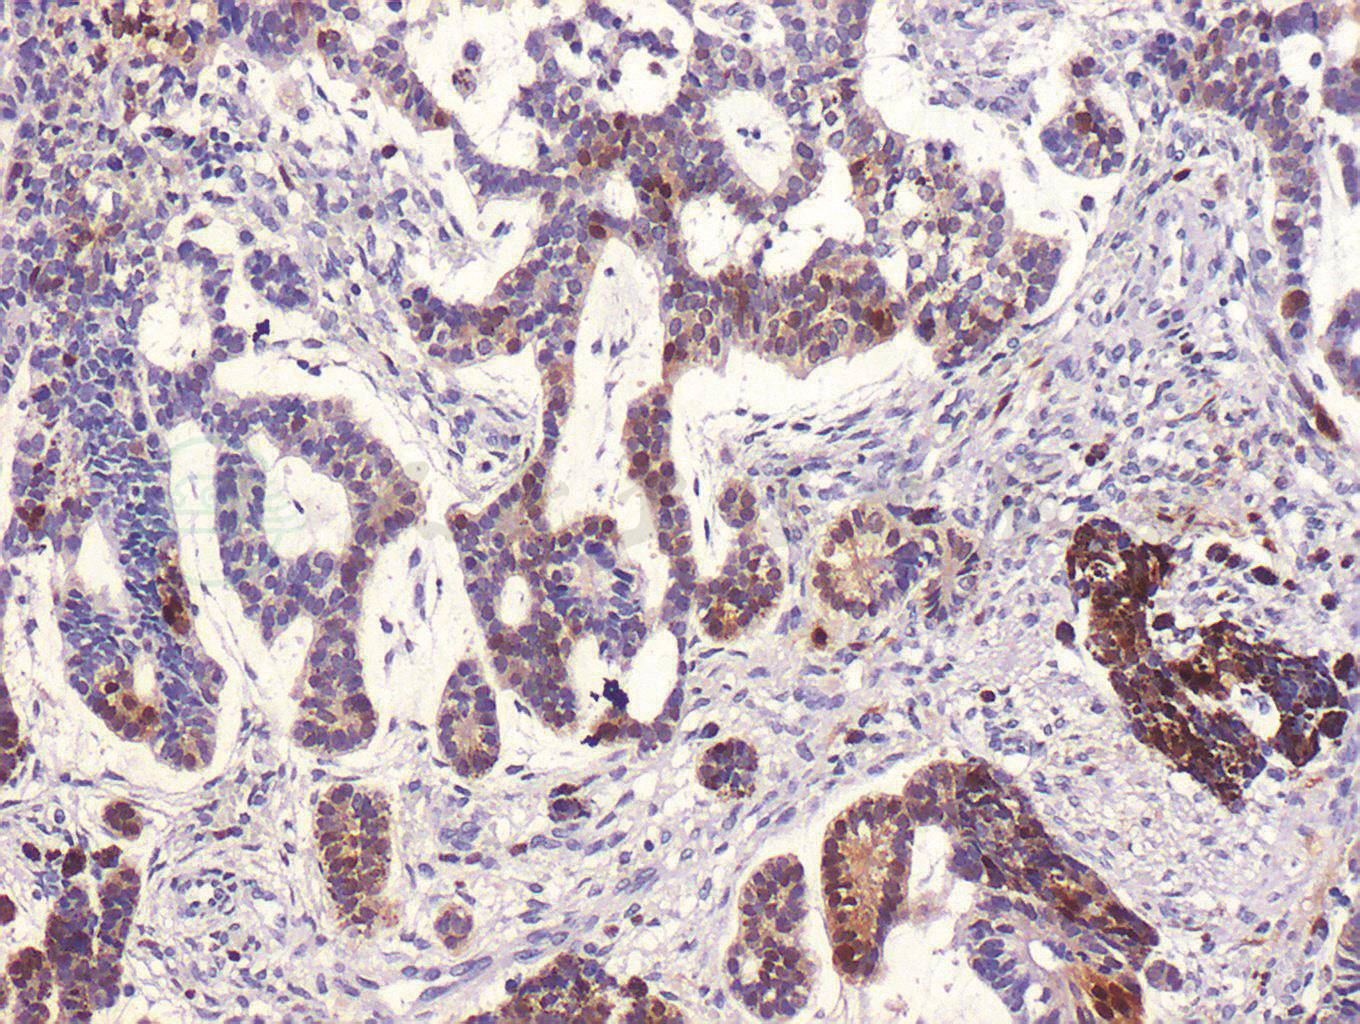

术后病理组织学检查结果显示左眼畸胎瘤样髓上皮瘤,肿瘤细胞生长活跃(图3)。肿瘤主要位于虹膜后的前玻璃体腔,视盘、筛板、筛板后视神经及视神经切除断端均未见明显肿瘤组织侵犯,肿瘤组织附近可见虹膜、睫状体色素上皮呈瘤样增生,并见软骨组织和纤维结缔组织增生,虹膜表面机化膜形成,虹膜周边粘连,继发视网膜脱离及视网膜下可见渗出。肿瘤组织行免疫组织化学染色检测显示:S-100(+),CD56(+),NSE(-),Syn(-),GFAP(-),Vimentin(-),Ki-67(-),Bcl-2(-),Melan-A(-),HMB45(+)(图4)。最终诊断为左眼畸胎瘤样髓上皮瘤。患儿术后1周出院,建议到儿科会诊,密切随访至今,病情稳定未见复发(图5)。

图3 左眼畸胎瘤样髓上皮瘤组织病理学检测(HE,100×)

髓上皮瘤的发病年龄较小,一般在5岁以内。该病多为单眼发病,极少有双眼发病者。眼内髓上皮瘤常以白瞳症、斜视、视力下降或眼痛就诊,因肿瘤常发生在睫状体区域,易继发青光眼。新生睫状体假膜是髓上皮瘤的特征性表现。这层假膜是由肿瘤细胞移行于晶状体后表面产生的一层胶原组织构成。MRI及UBM对诊断该病有一定的价值。髓上皮瘤的临床表现与视网膜母细胞瘤相类似,两者的鉴别诊断较为困难,导致病理诊断是鉴别两者的金标准。本例患儿的病理特征为肿瘤细胞生长活跃,肿瘤组织免疫组织化学检测S-100阳性。S-100为神经组织标志物,存在于神经组织,垂体、颈动脉体,肾上腺髓质、唾液腺、少数间叶组织内,常用于神经鞘瘤、恶性黑色素瘤、脂肪肉瘤、软骨肿瘤诊断等。结合病理组织学改变和免疫染色结果,本例患儿最终诊断为畸胎瘤样髓上皮瘤。